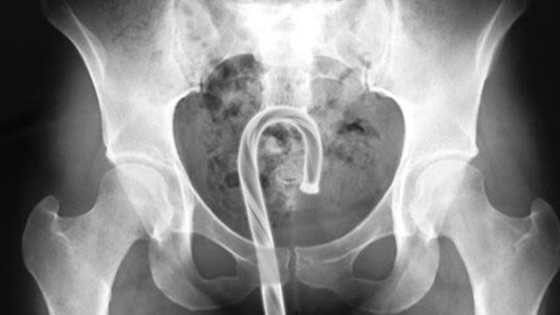

Комиссия США по безопасности потребительских товаров опубликовала список вещей, застрявших в американцах за год. Об этом сообщило издание Adequate Man. Журналисты упорядочили происшествия по отверстиям, куда попадали посторонние предметы. Согласно списку, в уши американцев среди прочего попадали: хлеб, батарейки, солома от веника, стружка от сточенного карандаша. Иногда врачи оставляли небольшие ремарки о случившемся вроде: «Бежал в палочкой в ухе, но упал им на стену» или «свернул бумажные полотенца и засунул в уши, потому что сосед очень громко храпел». В 2017 докторам пришлось вытащить из ноздрей пациентов следующие вещи: розовый воздушный шарик, соску для бутылочки, два магнита, каждый из которых был в своей ноздре. Из горла медики извлекали открытую английскую булавку, пасхальное яйцо, термометр для аквариума. Один из пациентов проглотил ручку, потому что «никто не обращал на него внимание», а другая — несколько скрепок, так как «ей так сказали инопланетяне». Нетипичные предметы врачи вытаскивали и из более деликатных мест. Например, из уретры за 2017 год врачи извлекли пластиковую ложку, кость домино, десятисантиметровую секс-игрушку и коаксиальный кабель. Из влагалища доктора доставали катафот для велосипеда, игрушечную волшебную палочку, наушники и глину. Из одной пациентки пришлось извлекать деньги и телефон, так как ее молодой человек поместил их туда во время секса. Наконец, из анального отверстия врачам пришлось извлечь мяч для гольфа, упаковку жевательного табака, игрушечную ракету и набалдашник для карниза. Пациенты объясняли происшествия разными причинами: лечением запора, облегчением симптомов геморроя, случайным падением в ванной, пьяными экспериментами с друзьями. Один американец и вовсе боролся с тревожностью, засунув бутылку с водой в анальное отверстие.